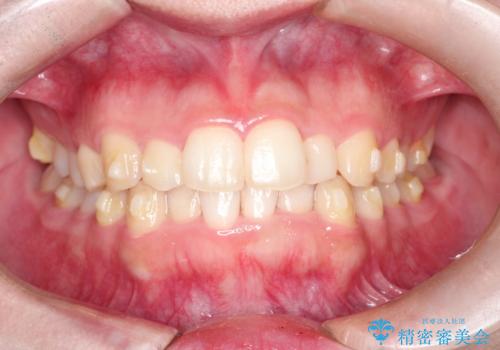

インビザラインでの前歯のガタガタの矯正

- 上下の前歯のがたつきを主訴に来院されました。

歯と歯の間をわずかに削りスペースを作り、インビザラインにて矯正治療を行うこととしました。

使用時間を守っていただけたので、スムーズに矯正を終了することができました。